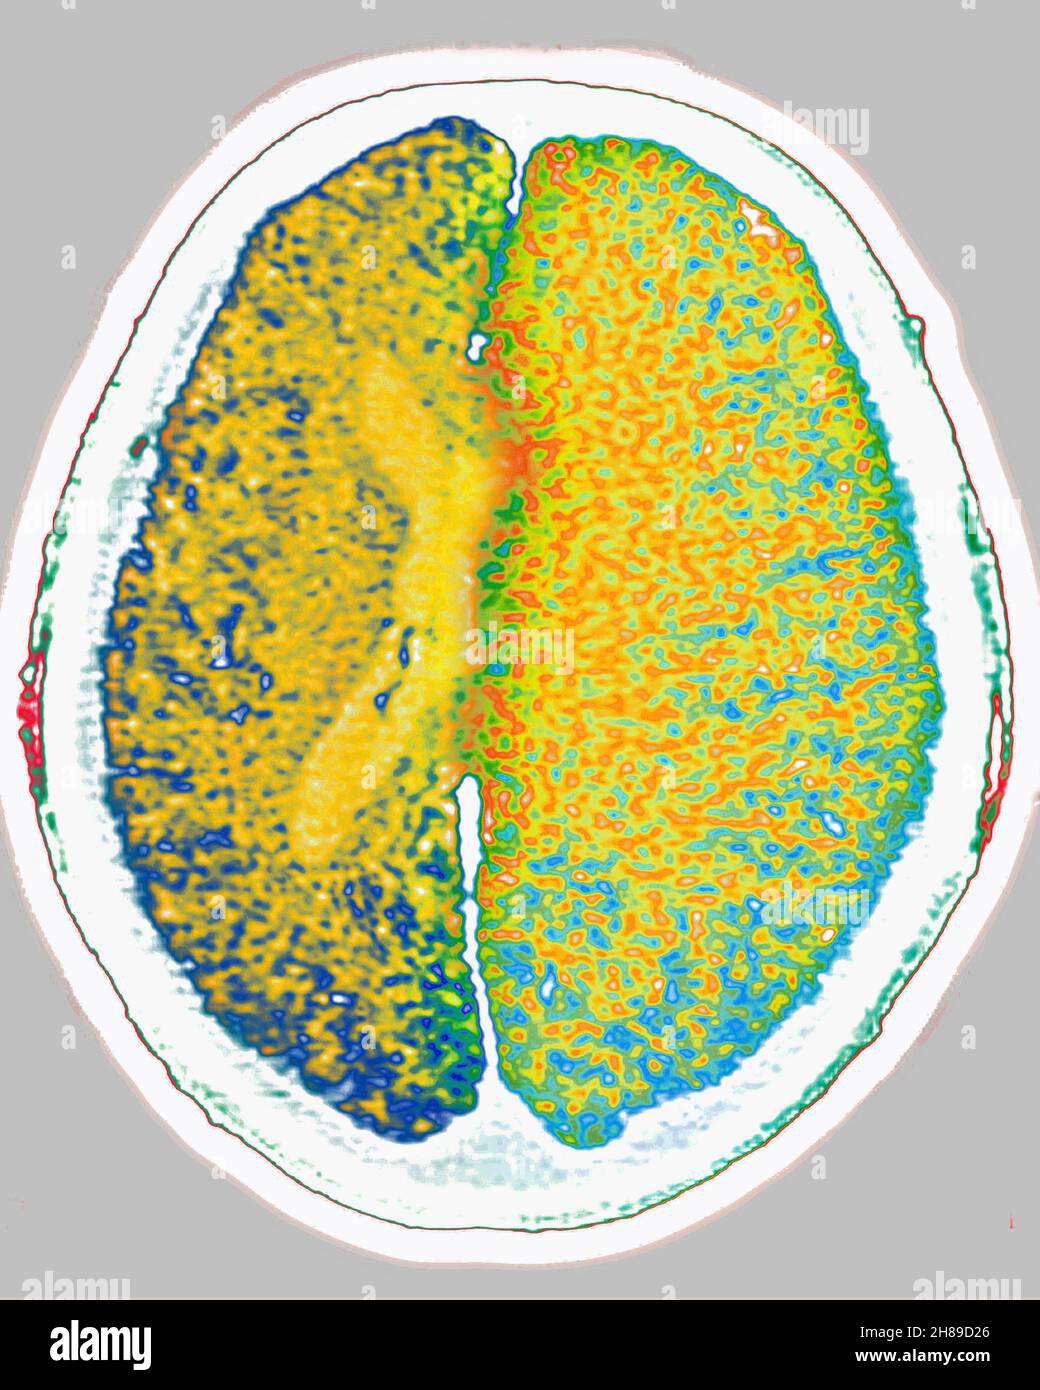

Œdème cérébral Banque D'Imageshttps://www.alamyimages.fr/image-license-details/?v=1https://www.alamyimages.fr/oedeme-cerebral-image452594638.html

Œdème cérébral Banque D'Imageshttps://www.alamyimages.fr/image-license-details/?v=1https://www.alamyimages.fr/oedeme-cerebral-image452594638.htmlRM2H89D26–Œdème cérébral

Œdème cérébral Banque D'Imageshttps://www.alamyimages.fr/image-license-details/?v=1https://www.alamyimages.fr/oedeme-cerebral-image452594632.html

Œdème cérébral Banque D'Imageshttps://www.alamyimages.fr/image-license-details/?v=1https://www.alamyimages.fr/oedeme-cerebral-image452594632.htmlRM2H89D20–Œdème cérébral